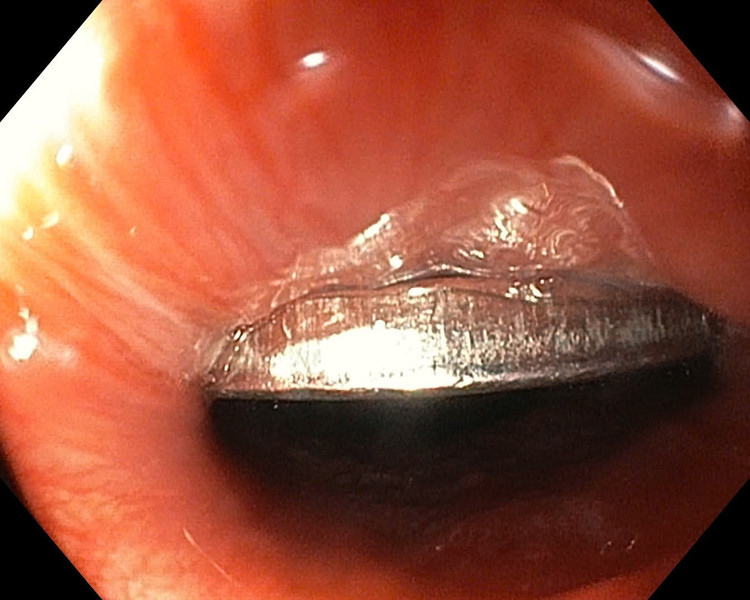

Dị vật đồng xu trong thực quản bệnh nhi - Ảnh BVCC

Ngay sau đó, bệnh nhi được chuyển đến Khoa Nội soi để thực hiện thủ thuật. Ê-kíp bác sĩ tiến hành nội soi dạ dày có gây mê, sử dụng dụng cụ chuyên dụng để tiếp cận và gắp dị vật ra ngoài. Sau khoảng thời gian ngắn, chiếc đồng xu đường kính 20mm đã được lấy ra an toàn.

Kiểm tra niêm mạc dạ dày – thực quản cho thấy không có tổn thương hay chảy máu. Bé tỉnh táo, sức khỏe ổn định và được xuất viện ngay trong đêm.